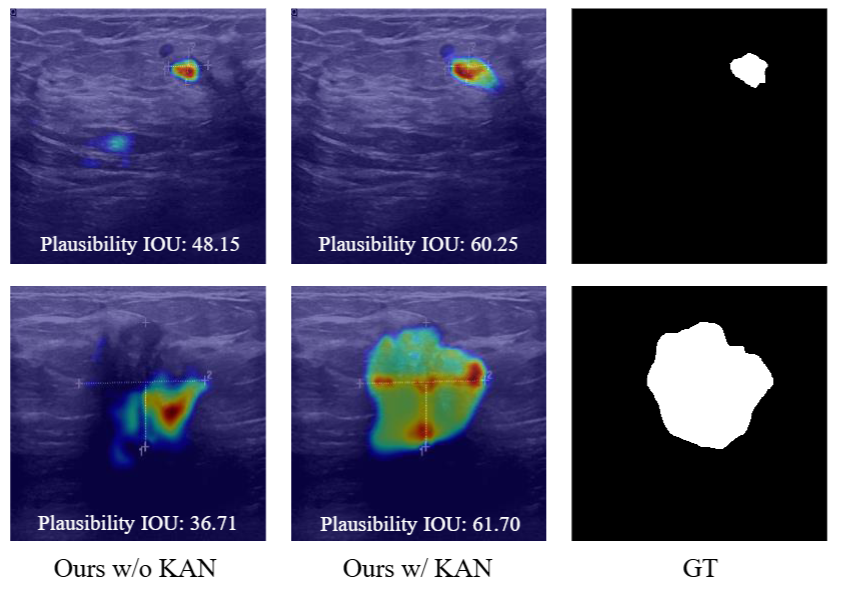

AAAI 2025 Top-1 most influential paper U-KAN Makes Strong Backbone for Medical Image Segmentation and Generation

Chenxin Li*, Xinyu Liu*, Wuyang Li*, Cheng Wang*, Hengyu Liu, Yifan Liu, Zhen Chen, Yixuan Yuan

project page/ paper/ code

Key Words: Kolmogorov-Arnold Networks; Medical Image Segmentation/Generation; Medical Backbone

Summary: We propose the first KAN-based medical backbone, U-KAN, which can be seamlessly integrated with existing medical image segmentation and generation models to boost their performance with minimal computational overhead. This work has been cited more than 250 times in one year.